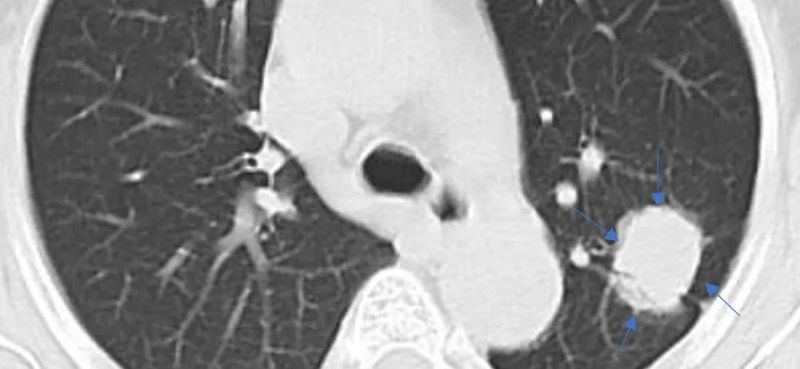

通过以下三张图片

可以有一个很好的理解

纯磨玻璃结节,可见内部血管影

混合磨玻璃结节,周围蓝色箭头所示为磨玻璃成分,中央红色箭头为实性成分

实性结节内部肺结构消失